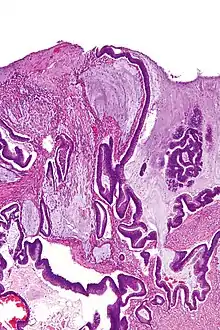

السرطانة المخاطية (بالإنجليزية: Mucinous carcinoma) هي نوع من السرطان الذي ينشأ من الخلايا الظهارية التي تبطن أعضاء داخلية معينة كما تبطن الجلد، وهي أيضًا تنتج الموسين (المكون الرئيسي للمخاط ).[1]

عندما توجد داخل الجلد فإن السرطانة المخاطية عادة ما يكون كتلة مستديرة مرتفعة حمراء وأحيانًا متقرحة، وعادة ما تكون موجودة على الرأس والعنق.[2] :669